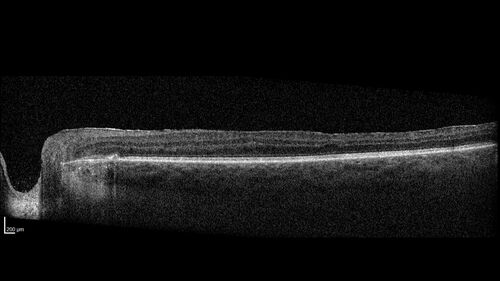

West Nile Virus Multifocal Choroiditis with later CNVM

77 year old female with vision loss in the left eye treated with Anti-VEGF